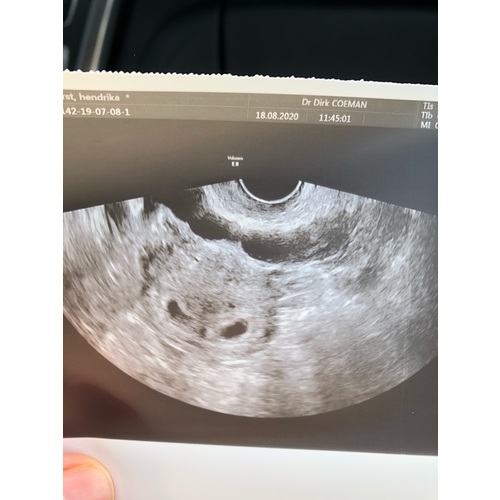

Deze was de mijne op 5w5, 2 vruchtzakjes en geen kindjes. Inmiddels toch al 23 weken zwanger van 2 meisjes. Laat de moed niet zakken!

Dit was mijn echo 5+5 ( er staat geloof ik ander termijn op , ik was echt veel terug gezet, door een gemiste menstruatie die dus eigenlijk gewoon gemist was en geen zwangerschap was )

Ze twijfelden wel of het goed zat, want groeide eerst ook niet lekker, met 7 weken terug gegaan voor een echo en het was gewoon gegroeid en zit prima ! Onderhand 30+4 van ons mannetje !